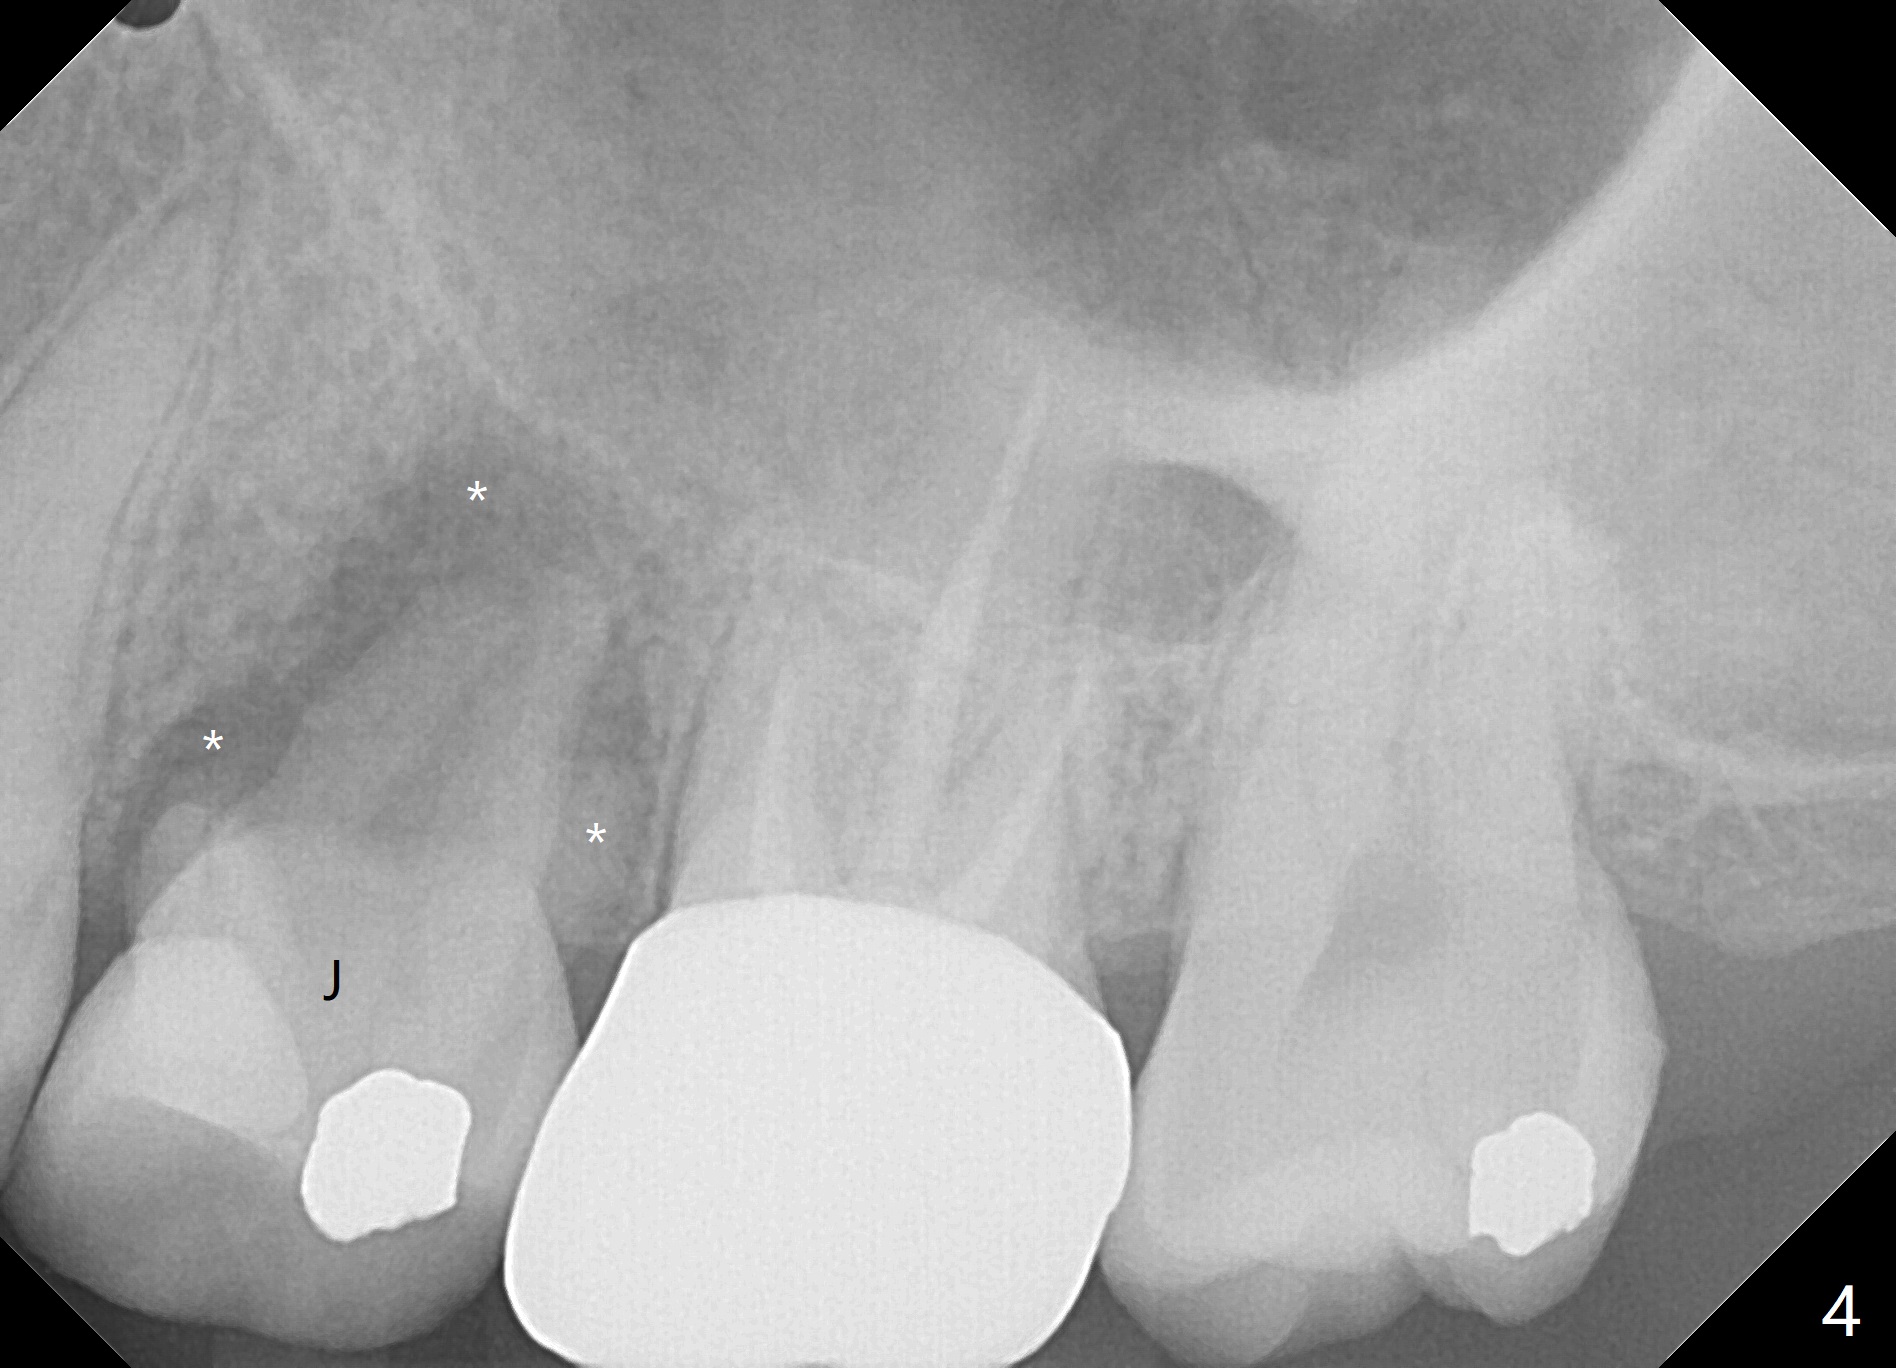

A 42-year-old woman requests extraction of the upper left 2nd primary molar with abscess (Fig.1,3,4). To avoid implants (for #30 as well in Fig.2) and improves cosmetics (anterior crowding), she chooses orthodontics with extraction of 2 more teeth in the other 2 quadrants. It seems necessary to have socket preservation so that the neighboring teeth have the bone to move to (Fig.5 without buccal plate collapse). In fact the coronal half of the buccal plate is resorbed. The bone regeneration is also important in case she changes her mind and ends up needing an implant. Return to Trajectory Xin Wei, DDS, PhD, MS 1st edition 05/17/2019, last revision 05/19/2019